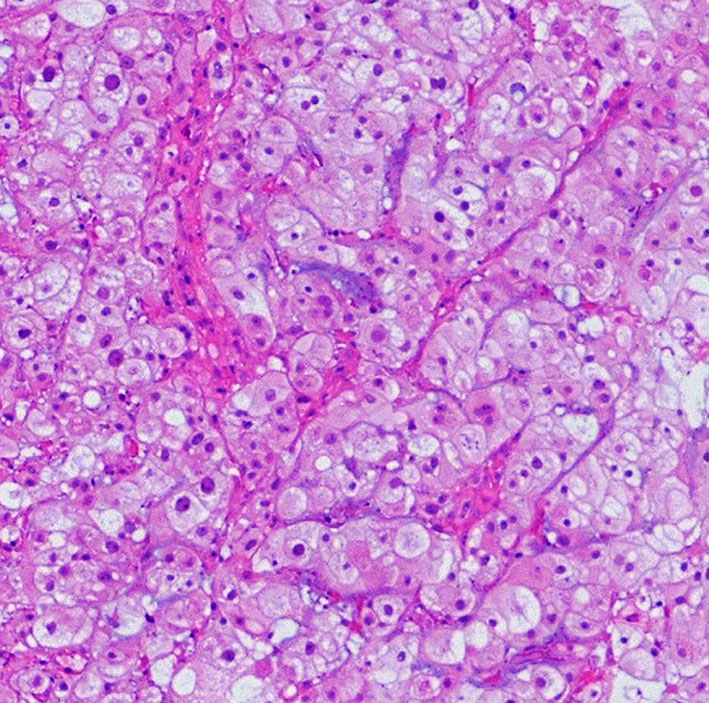

病理像です。軟骨様組織を混在しない純粋な脊索腫です。核を中心にして大きな丸い細胞体には空胞が目立ちます。空胞腫瘍細胞 physaliphorous cellsのシート状配列が特徴的です。左上の写真にわずかに粘液状間質(青く染まるところ)がみえます。

病理像は脊索腫と区別がつかない indistinguishableことがあります。腫瘍周囲組織への浸潤像の有無だけが鑑別点であるという意見もあります。